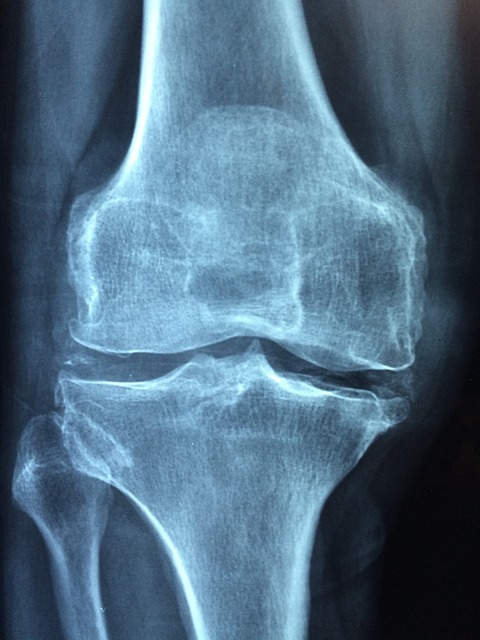

6. 골밀도 증가

뼈의 미세 구조를 강화하고 골밀도를 높일 수 있습니다.

1. 관절 및 근육 통증

적절한 운동은 근육을 강화하고 건강한 뼈를 유지하는 데 도움이 됩니다.

특히 골밀도를 높이는 유산소 운동 강도 있는 운동이 좋습니다.